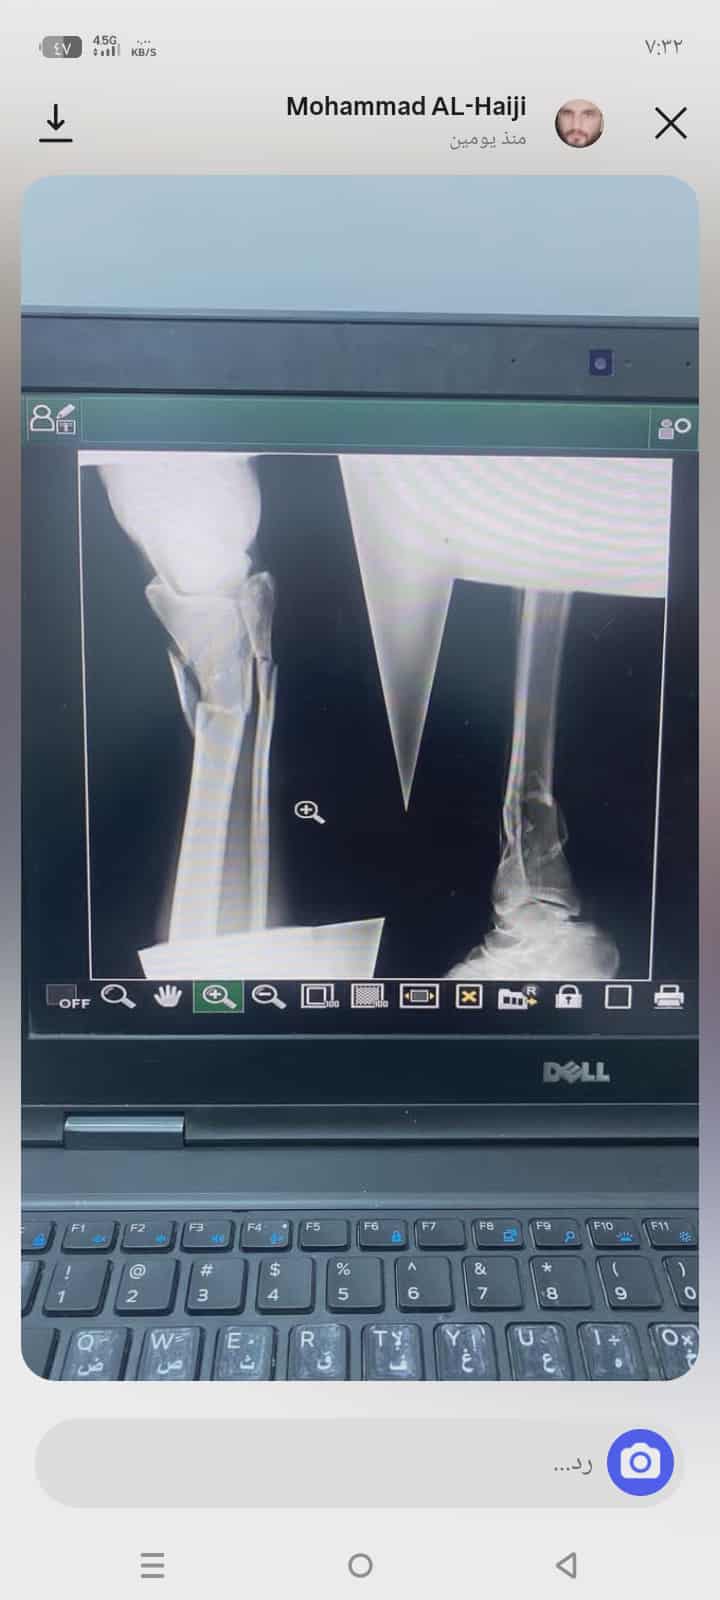

كسور في الساق وتم تركيب ثلاث اسياخ مع تركيب جبصين